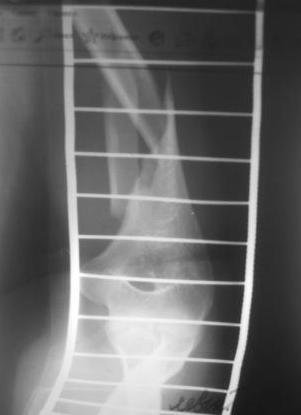

Перелом нестабильный, тактика - если позволяет сосояние больной, оперативное лечение. Как пример см. ниже, можно без скобы - стяжки с ЭПФ.

Да, как раз блокированная пластина и стоит, не синтезовская метадиафизарная, Рыбинская, но на порядок дешевле, а профилактика всех осложнений - в данном конкретном случае, начало ранней на вторые сутки - после удаления дренажа разработки движений в смежных суставах. Если же идти с ревизией т.е. всё равно, открыто как вариант небольших разрезов при поперечном переломе можно и комбинированный мос (см.на вкладыше), хотя думаю для такого способа перелом всётаки низковат.

Всё правильно, просто я несколько разрозненно пытался сказать на частных примерах, то , что Вы систематизировали. Совершенно верно данный перелом можно и так и эдак, наиболее оптимально антеградное штифтование, хотя я бы предпочёл пластину LCP(просто - ну лучше у меня это получается и всё, а больному не вредит тот же функциональный способ). А низковато для неблокированного штифтования с конструкциями с термомеханической памятью, то, что представленно на втором снимке.

По поводу представленного больного, соглашусь, что в дистальном отломке вполне уместится штифт-эксперт, хотя чтобы провести репозицию + заблокировать все 4 отверстия, придется здорово помять окружающие кость ткани.

По поводу представленного больного, соглашусь, что в дистальном отломке вполне уместится штифт-эксперт,

хотя чтобы провести репозицию + заблокировать все 4 отверстия, придется здорово помять окружающие кость ткани.

А зачем все 4?.. да и разве их там 4 (дистально)? Достаточно 2-х.